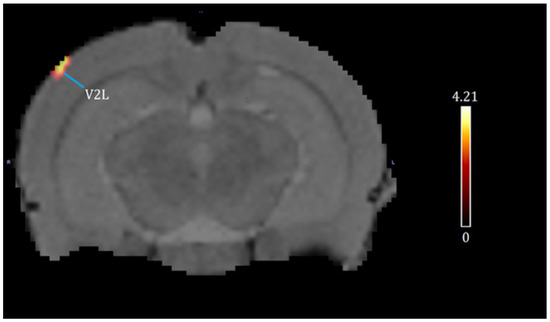

| Brain Region | Cluster Location (General) | Medial–Lateral (mm) | Dorsal–Ventral (mm) | Anterior–Posterior (mm) | t-Value | z-Score | KE |

|---|---|---|---|---|---|---|---|

| V2L | Somatosensory Cortex | −5.2 | 1.2 | −6.8 | 4.21 | 3.52 | 229 |